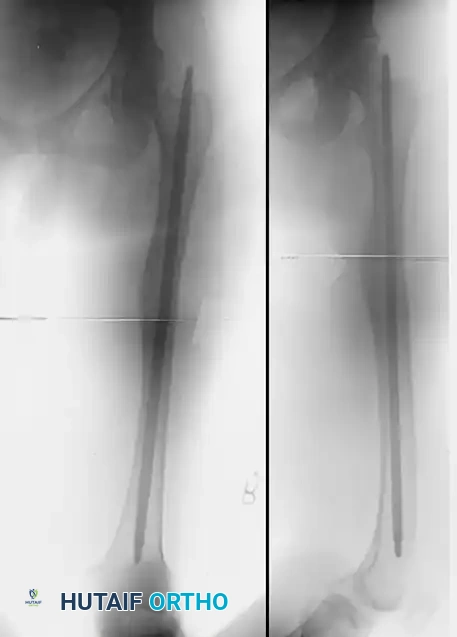

Image

FIGURE 58-22 A: Rotational malunion of the femur following unlocked intramedullary nailing.

FIGURE 58-22 B: Intraoperative correction of the malunion utilizing a proximal femoral derotational osteotomy and subsequent locked intramedullary nailing.

FIGURE 58-22 C: Radiographic evidence of a fully healed osteotomy with restored axial alignment.